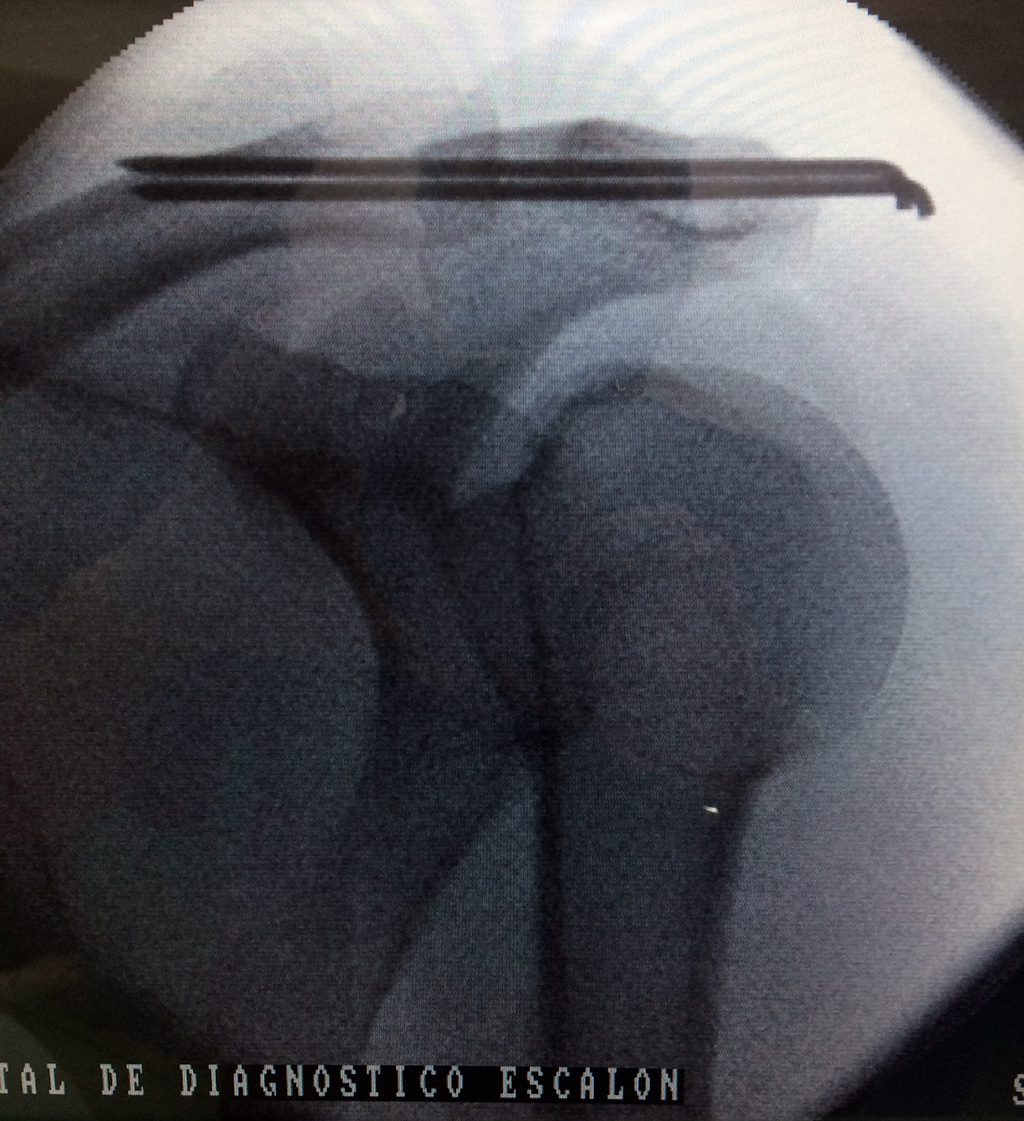

Cirugía de Fémur - Clavícula

La clavícula es un hueso largo, con forma de "S" itálica, situado en la parte anterosuperior del tórax. Junto con la escápula forman la cintura escapular. Se puede palpar por toda su longitud y se extiende del esternón al acromion de la escápula, siguiendo una dirección oblicua lateral y posterior.

Se considera el único medio de unión entre el miembro superior y el tórax. A pesar de su aspecto, similar al de un hueso largo, posee una estructura semejante a la de un hueso plano, ya que carece de epífisis y de diáfisis, lo que la harían entrar dentro de la clasificación de hueso largo. Carece de un canal medular propiamente dicho.